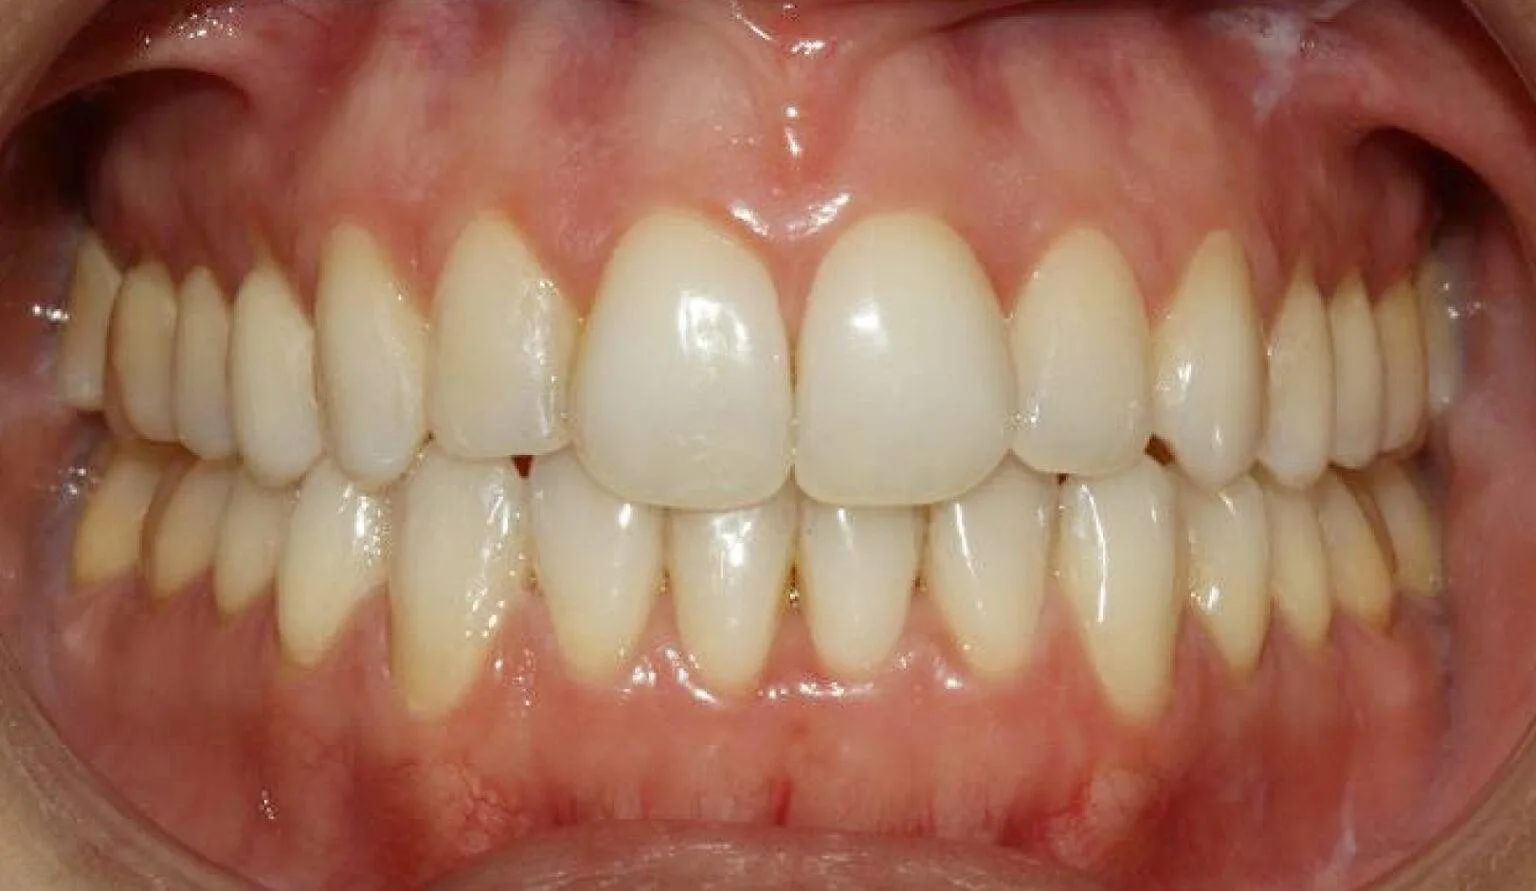

Before & After Invisalign® Gallery